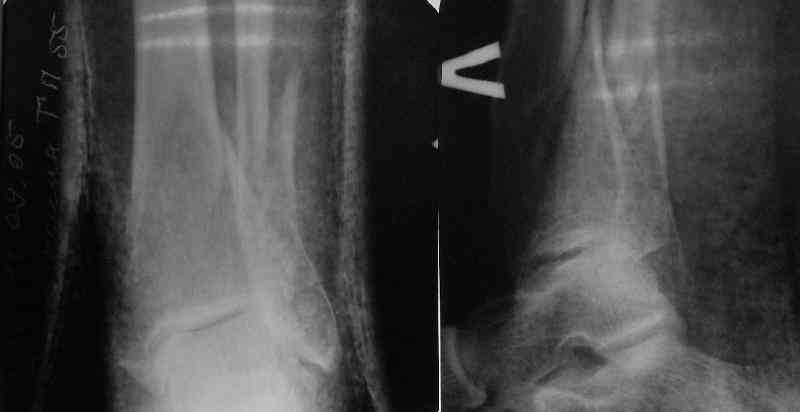

A typical case is attached, also an image with intra-op reduction obtained by a small wire distractor, in the moment of insertion a Poller wire in AP direction. Fixation by a SIGN nail. Despite the fibula was not fixed healing was obtained with the unchanged alignment.

In delayed cases acute length restoration performed only in the tibia may leave the fibula shortened thus change the mortise. So it is reasonable to restore length of both bones simultaneously by distractor and fix the fibula not with open reduction and plating but just by a single perQ screw. Example attached.